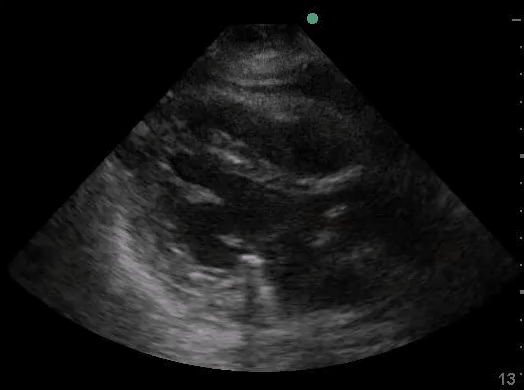

Definitions of cardiac activity and standstill vary across the literature. [14] Most definitions describe ventricular contractility and a decrease in left ventricular chamber size, though discrepancies exist with the identification of atrial or valve flutter. Ultrasound operators may also mistake movement of the chest structures with mechanical ventilation as cardiac activity. Furthermore, weak myocardial contraction, profound bradycardia, or fine ventricular fibrillation can also be confused as cardiac standstill. Examples of cardiac standstill and a weak, bradycardic rhythm are highlighted in Figure 2.

Figure 2. A) Parasternal long view with cardiac standstill. B) Subxiphoid view highlighting weak cardiac activity.